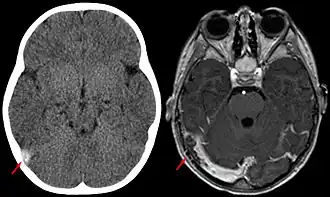

Door de variatie in de klinische presentatie is het soms moeilijk om de diagnose te stellen. De diagnose CVT kan worden vastgesteld met behulp van een scan van het hoofd; een CT-venografie, of MRI hersenen in combinatie met een MR-venografie. Slechts in zeldzame gevallen is een conventionele angiografie noodzakelijk. Bij de helft van de patiënten met CVT is er op de scan een veneus herseninfarct zichtbaar, wat vaak bestaat uit een combinatie van oedeem en kleinere hersenbloedingen.